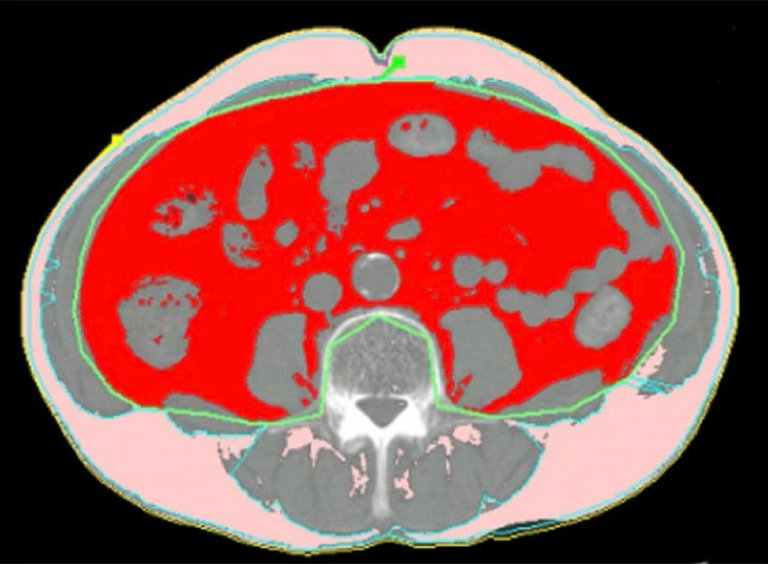

체지방 CT (body fat CT) 검사를 통해 내장 지방을 직접 측정하는 방법입니다.

4, 5척추 부위에서 피하지방과 내장지방의 면적을 정밀 측정합니다.

복부 비만을 평가하는 가장 정확한 방법입니다.

내장 지방이 100 cm2 이상이고 내장지방과 피하지방의 비율이 0.4 이상이면 내장지방형 비만으로 진단합니다.